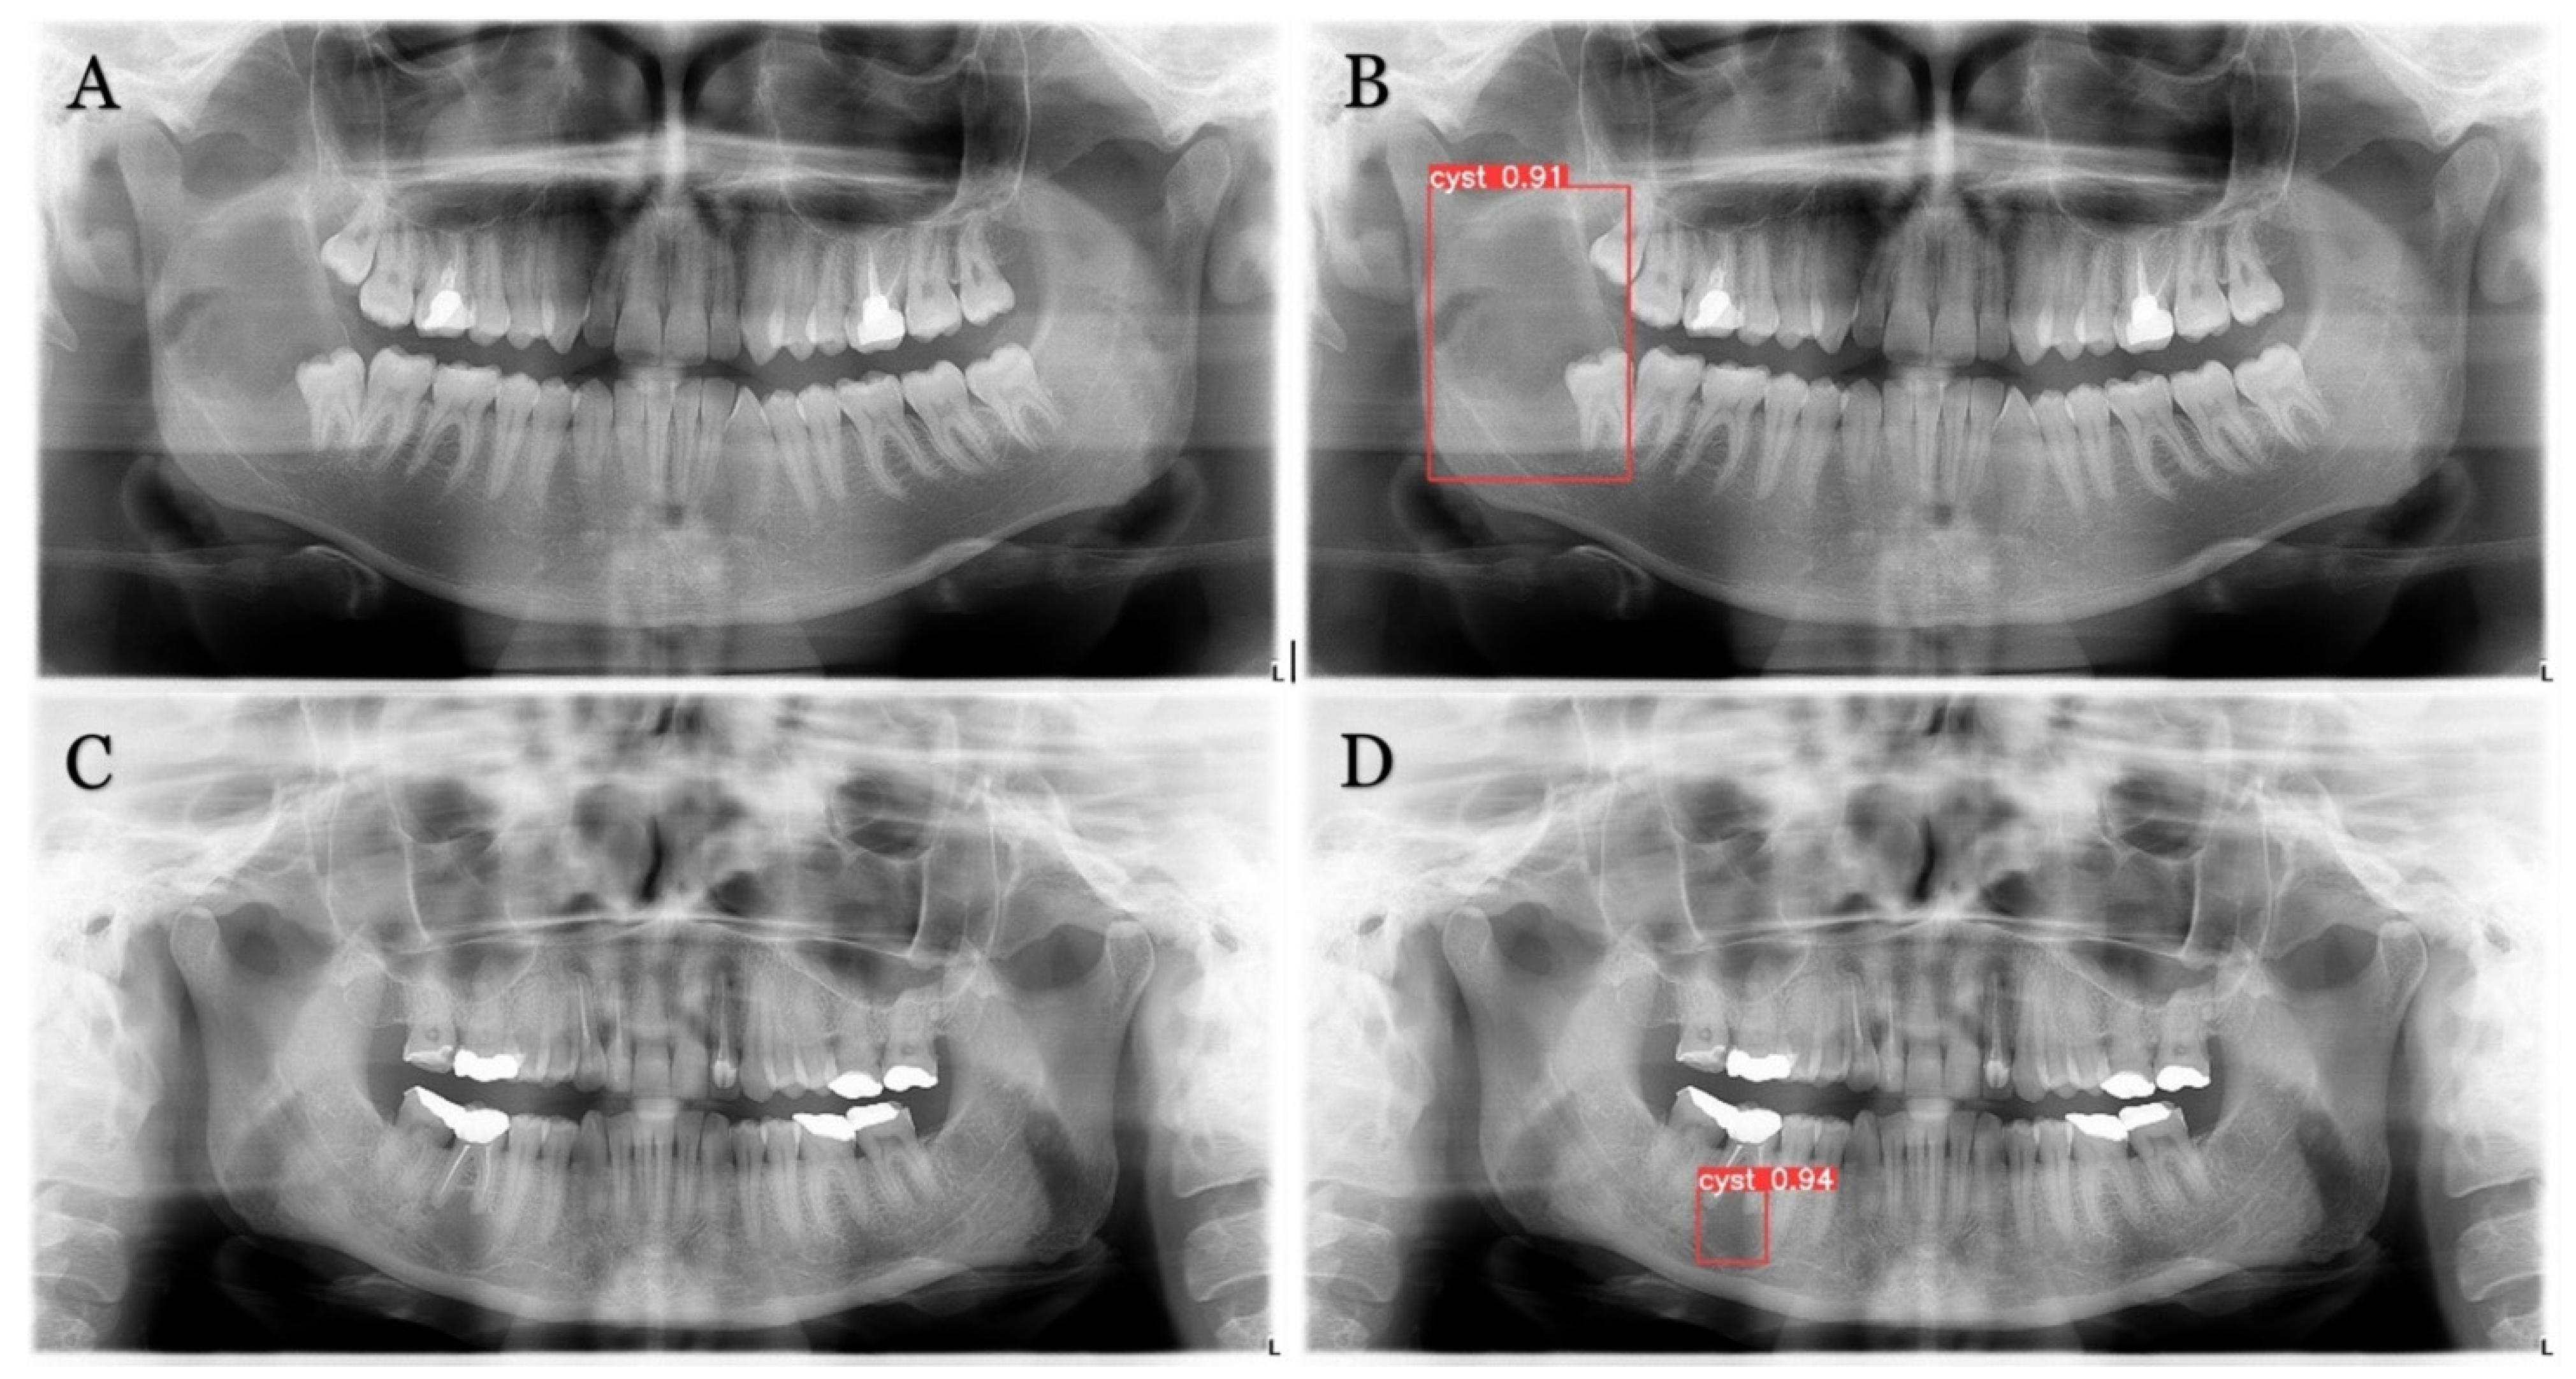

The trained model is capable of predicting bounding boxes, segmentation masks and probabilities, as shown in Figure 4 and Figure 5.

Figure 4. Model detection prediction of the radiolucent lesion in the lower jaw. (A), lesion in the ramus of the mandible (B), model successful detection of 91% (C), lesion in the corpus of the mandible (D), successful detection of 94%.